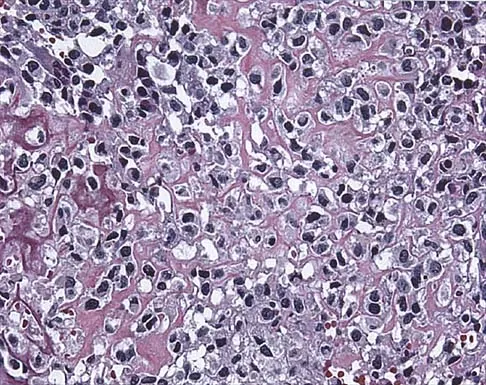

A 10-year-old boy has a painful thigh mass. A radiograph, MRI scan, and biopsy specimen are shown in Figures 42a through 42c. What is the most likely diagnosis?

Explanation

A destructive mixed lytic and blastic metaphyseal lesion with a large soft-tissue mass in an adolescent is most likely an osteosarcoma until proven otherwise. The epicenter of the tumor is on the surface of the bone, most likely involves the periosteum, and is more likely to be chondroblastic in nature. Parosteal osteosarcoma is a low-grade tumor, much more radiodense, usually smaller, and found in the posterior distal femur of middle-aged patients. Chondrosarcomas are distinctly rare in childhood.